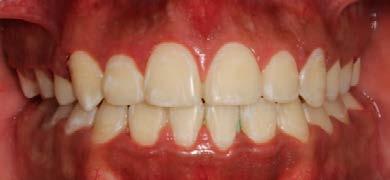

La duración del tratamiento fue de 1 año 9 meses, manteniendo el perfil facial estético y funcional (Figura 9).

Estudios intraorales finales

En las fotografías intraorales finales se ve la corrección del apiñamiento maxilar y mandibular, la forma de las arcadas es ovalada, se consiguió guía de desoclusión canina derecha e izquierda, la mordida profunda

anterior (Figura 10), la estabilidad oclusal, la máxima intercuspidación, el paralelismo radicular y oclusión funcional, el cierre de diastema ante rior, las líneas medias superior-infe rior coincidieron ambas con la facial.